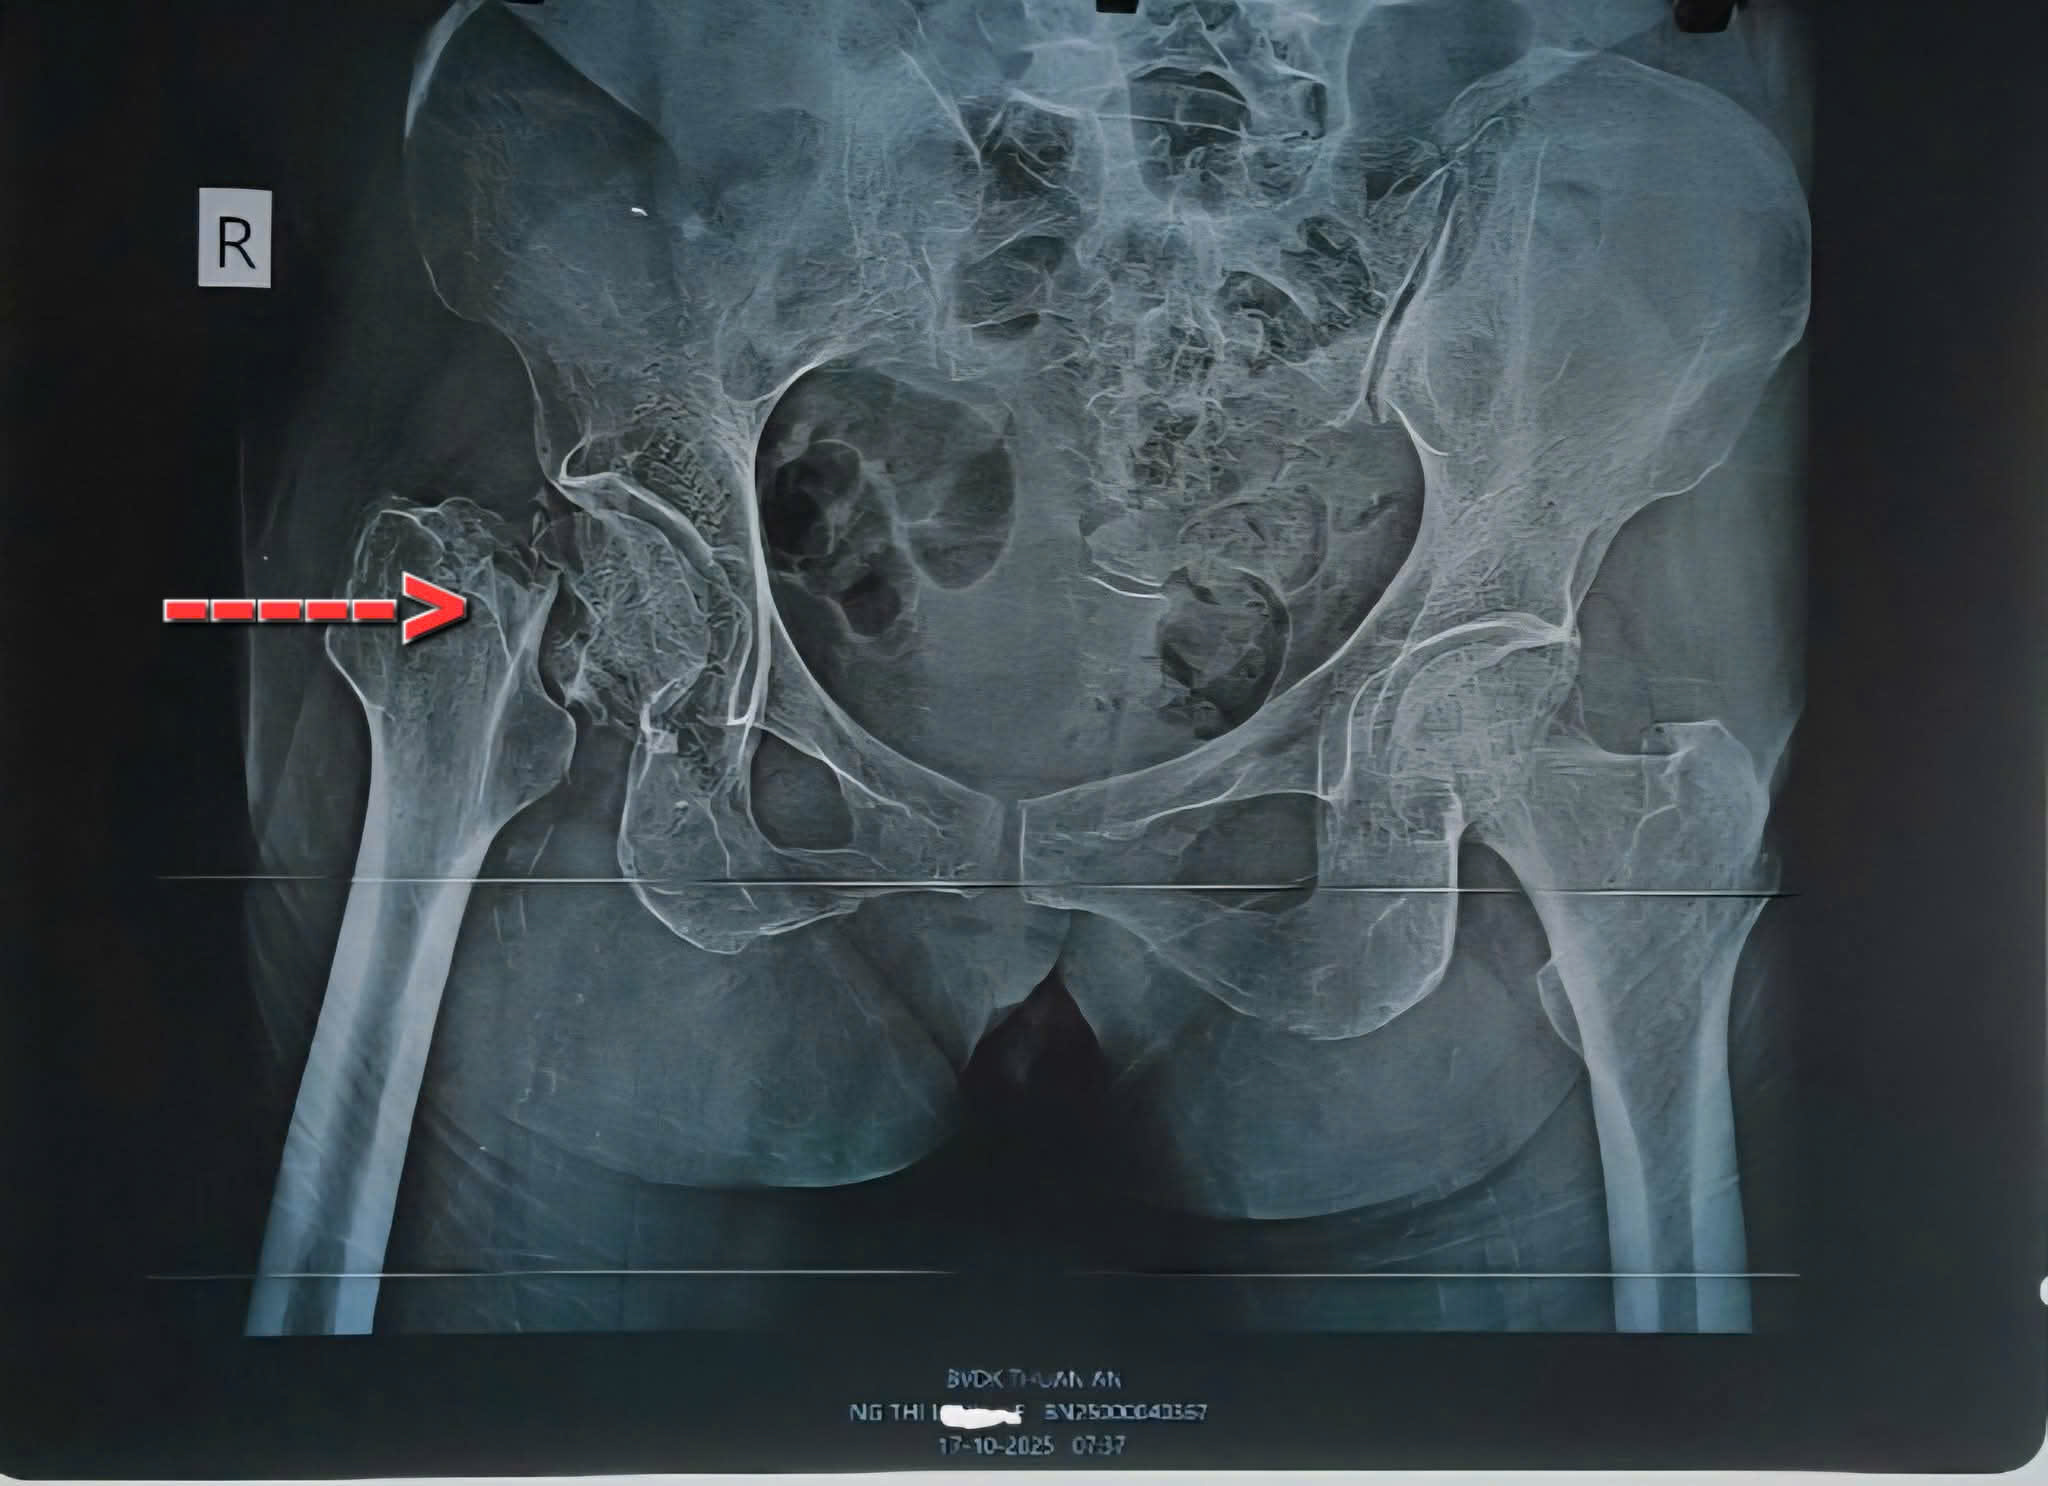

Gãy cổ xương đùi bên phải, Sau mổ thay khớp háng nhân tạo bán phần bên phải. Bệnh nhân bớt đau nhiều, có thể tự ngồi dậy sẽ tập đi lại trong vài ngày tới

Bệnh nhân nữ 74 tuổi gãy cổ xương đùi bên phải do té ngã và Sau mổ thay khớp háng nhân tạo bán phần bên phải. Bệnh nhân bớt đau nhiều, có thể tự ngồi dậy sẽ tập đi lại trong vài ngày tới